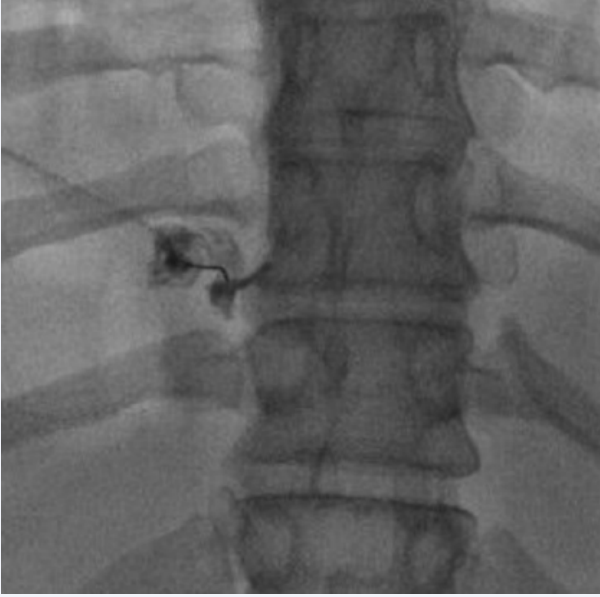

Thoracic sympathetic blocks

Thoracic sympathetic blocks (TSBs) (Figure 3) are usually helpful to diagnose and treat chronic benign and malignant thoracic and mediastinal pain syndromes, including neuropathic pain, chest wall pain, thoracic visceral pain, herpes zoster, postherpetic pain, phantom breast pain.

Left side thoracic sympathetic injection under fluoroscopy  with contrast.

Figure 3: Left side thoracic sympathetic injection under fluoroscopy with contrast

Diagnostic and therapeutic blocks of the sympathetic chain from T2-8 can be used in patients with severe intractable pain caused by cancer of the esophagus heart, bronchi, trachea, lung, pleura or other chronic esophageal pain [32,33].

Anatomically the sympathetic trunks are two ganglionated nerve structures that extend the entire length of the vertebral column. The thoracic part of the sympathetic chain runs downward and leaves the thorax behind the medial arcuate ligament [34].